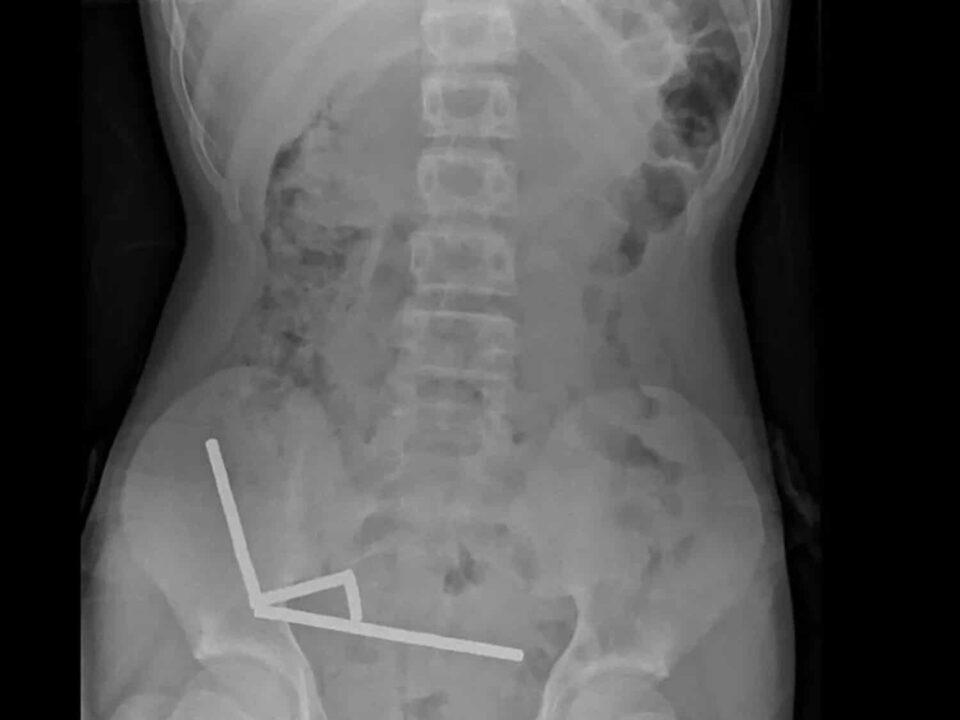

ئەم موگناتیسانە، کە لە مانگی یەکی ٢٠١٣ەوە لە نیوزیلەند قەدەغە کراون، لە ڕێگەی پلاتفۆرمی کڕینی ئۆنلاینی “تیمۆ”وە کڕدرابوون. وێنە تیشکییەکان نیشانیان دا کە ئەم موگناتیسانە لە چوار هێڵی ڕاستدا لە ڕیخۆڵەی گەنجەکەدا کۆبوونەتەوە و بەهۆی هێزی موگناتیسییەوە، بەشە جیاوازەکانی ڕیخۆڵە پێکەوە نووسابوون.

فشاری دروستبوو به هۆی موگناتیسەکانەوە بووە هۆی مردنی شانەکان لە چوار ناوچەی ڕیخۆڵە بچووک. نەشتەرگەرەکان بە ئەنجامدانی نەشتەرگەری، موگناتیسەکان و شانە مردووەکانیان لابرد و گەنجەکە دوای هەشت ڕۆژ مانەوە لە نەخۆشخانە توانی بگەڕێتەوە ماڵەوە. پزیشکان هۆشدارییان دا کە ئەم جۆرە نەشتەرگەرییانە لەوانەیە لە داهاتوودا کێشەی وەک گیرانی ڕیخۆڵە، فتق و ئازاری درێژخایەن دروست بکەن.